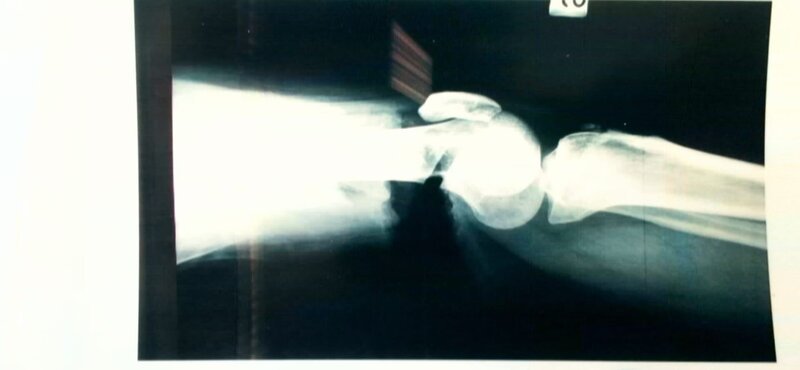

Das Röntgenbild des Oberschenkelknochens des Opfers: Es zeigt einen starken Einschnitt im Knochen. – Bild: ZDF und Polizei Bozen

Das Röntgenbild des Oberschenkelknochens des Opfers: Es zeigt einen starken Einschnitt im Knochen.